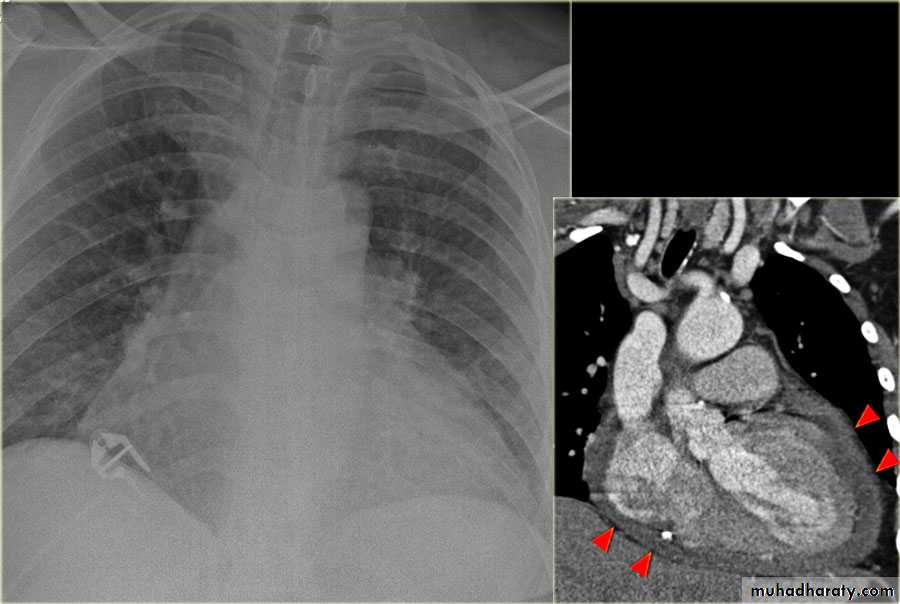

Fall from the 2nd floor